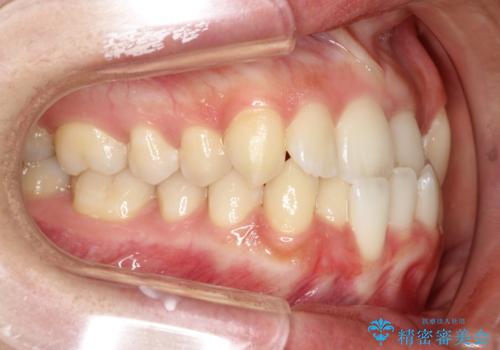

- 前歯の歯並びの改善を希望され来院された患者様です。

初診時の歯並びの状態としては、上下ともに全体に及ぶの中等度以上のがたつき(叢生)があり、前歯数本が反対交合の状態でした。

強い叢生がありましたが、抜歯は行わず上下顎ともに、主に歯列弓の拡大とディスキング(歯と歯の間に隙間を作る処置)を行い叢生を改善しました。